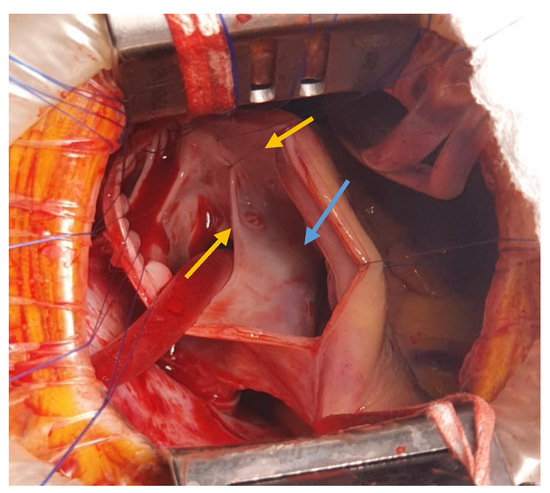

The interatrial defect was exposed through a right atriotomy extended across the cavoatrial junction into the superior vena cava. The examination of the right atrium cavity revealed an atrial septal defect in the proximity of the SVC and both right pulmonary veins draining into the SVC, proximally (Figure 3 and Figure 4).

Figure 4. Intra-atrial look of the SV-ASD with PAPVD (pulmonary veins ostia—yellow arrows; ASD—blue arrow).